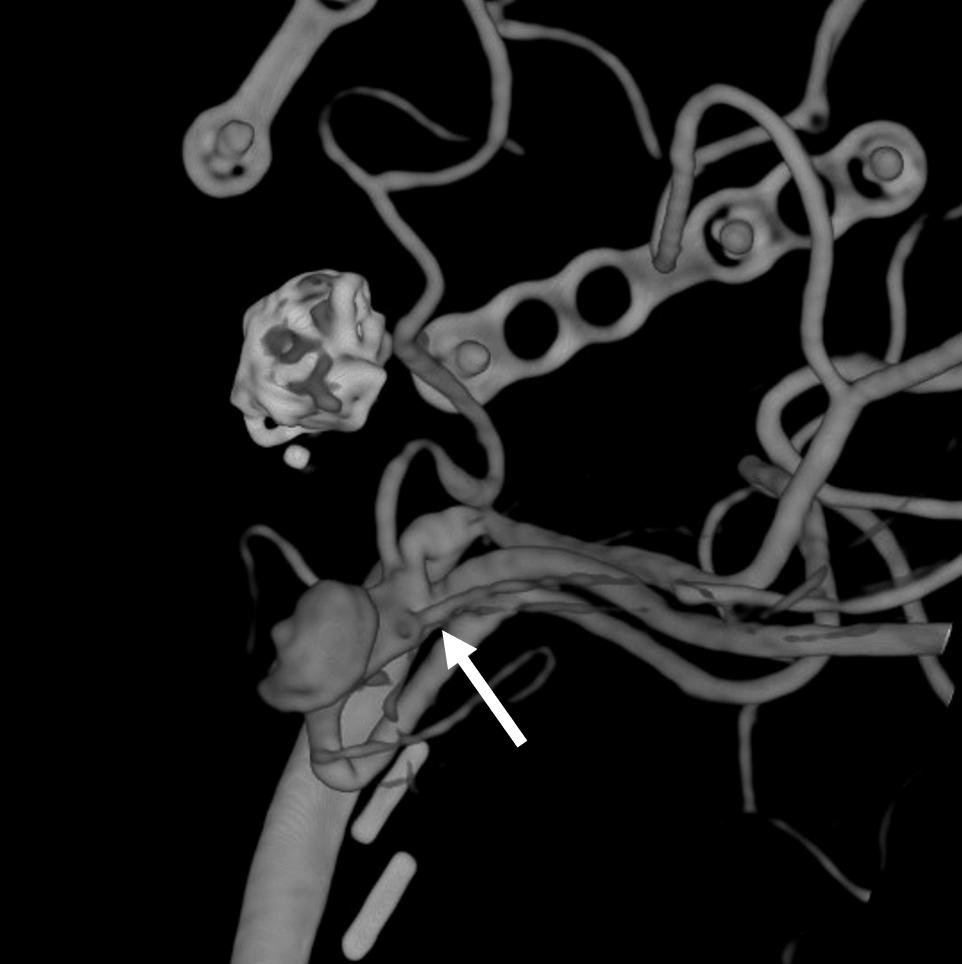

3 months follow-up control with 3D reconstruction of the bypass (3D 5 seconds protocol with 19 cm FOV, pure contrast (300 mg/ml) manual injection), confirming the origin of the M2 perforators (arrow) What else is new in the image since the bypass?